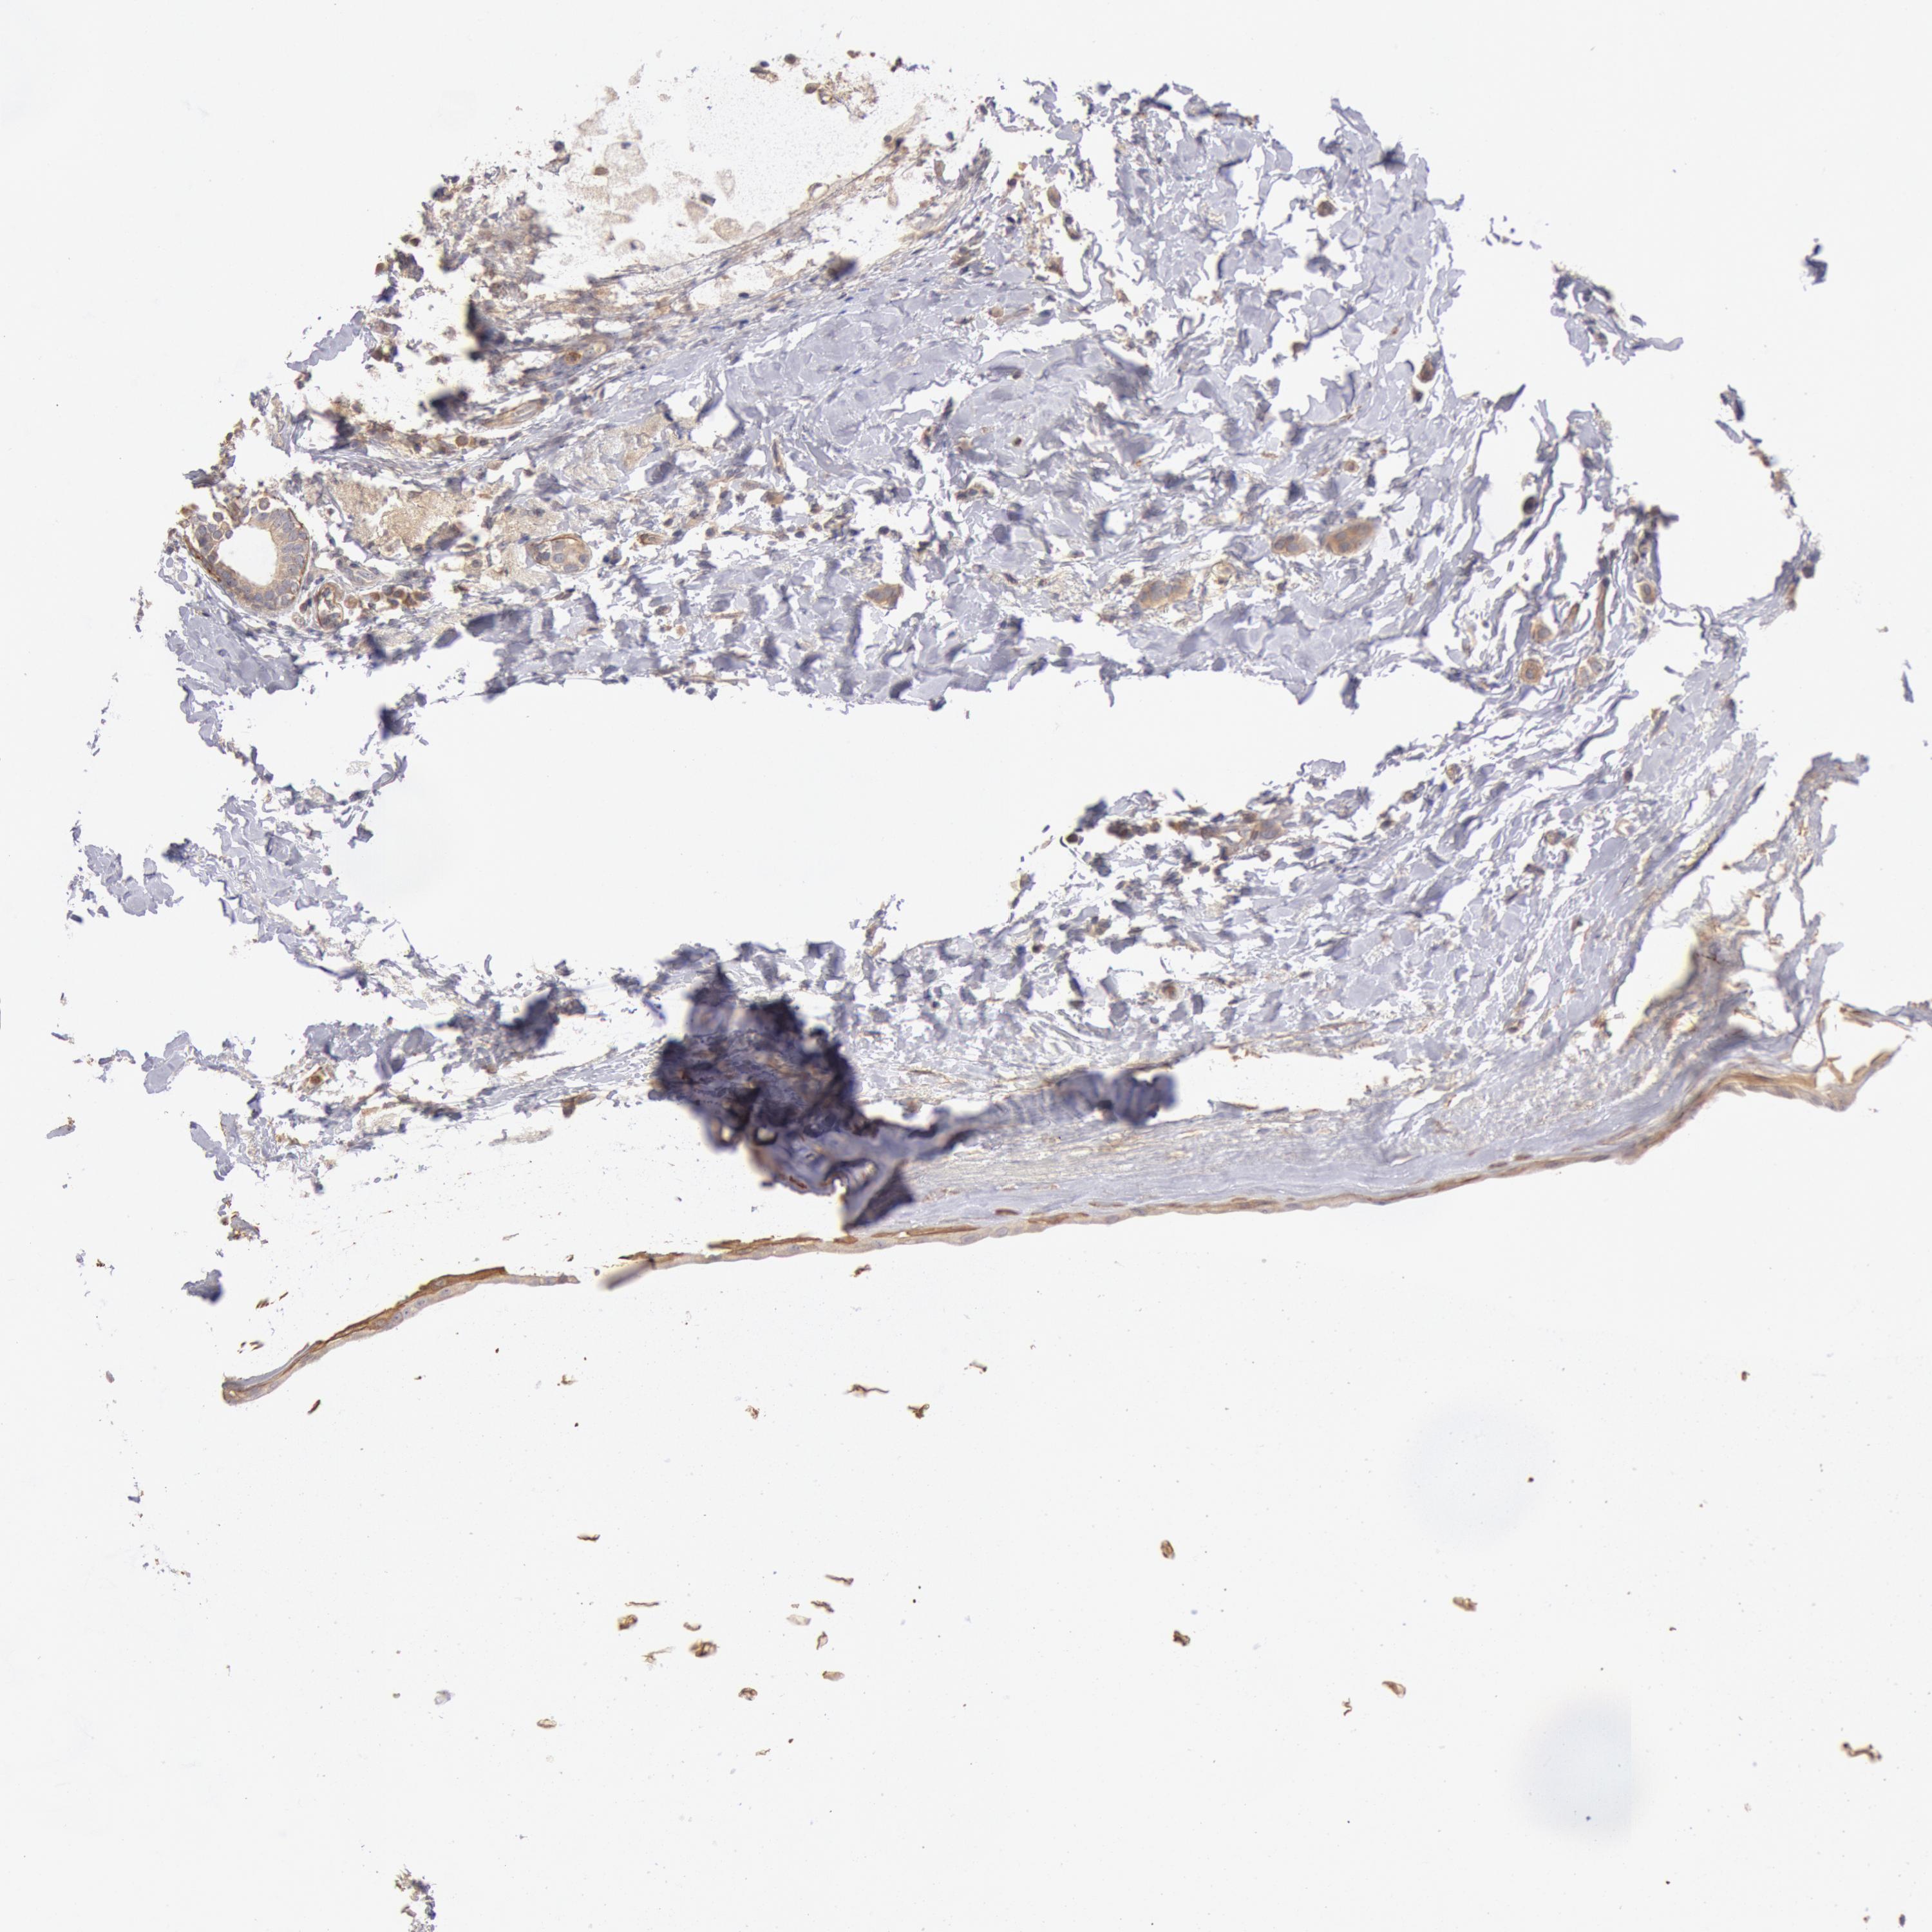

BRCA TCGA BRCA VALIDATION PROTEIN EXPRESSION

ANTIBODIES

AND

VALIDATION